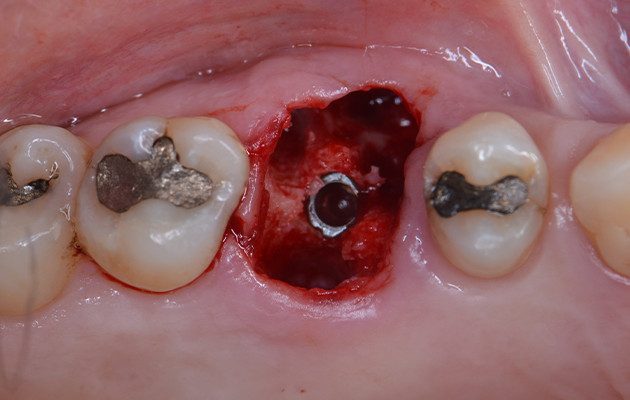

8 | Detalhe do torque de inserção obtido durante a instalação do Implante

9 | Posição do Implante ao final da instalação.